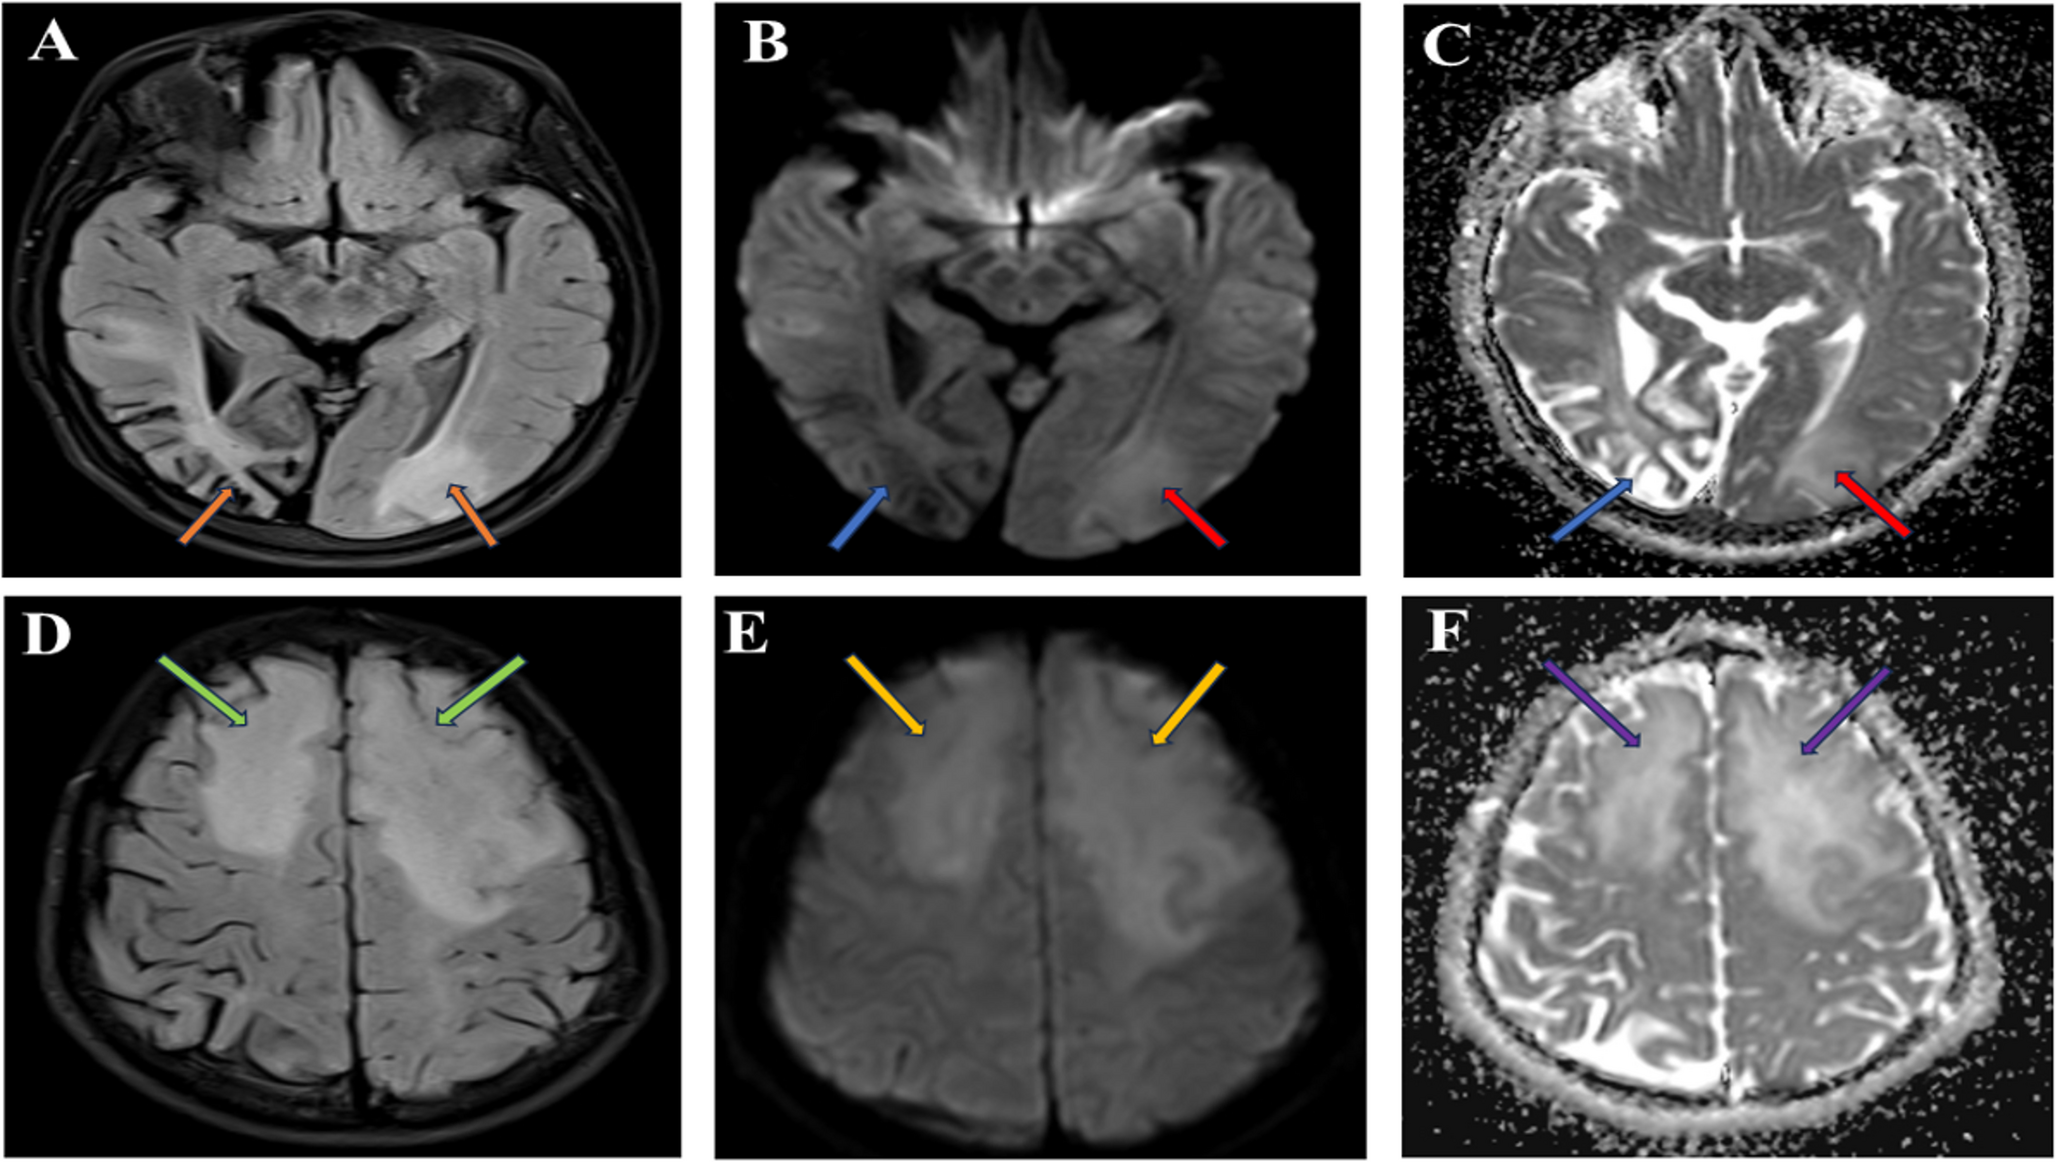

Purpose: Bilateral damage of fornix bodies has been reported in a few cases of brain tumors and in exceptional cases of ischemia. Methods: a 73-year-old man presented with acute right ataxic hemiparesis and right hypoesthesia. Brain MRI showed an acute ischemia of both fornix bodies and of the left posterior lateral thalamus, along with a septum pellucidum (SP) cyst. MR angiography revealed a 7-mm long stenosis of the initial P2 of the left posterior cerebral artery. Neuropsychological evaluation documented an amnestic syndrome. Fornix bodies and posterolateral thalamus are supplied by the medial and lateral branches of posterior choroidal artery, arising from the initial P2. As our patient presented a single intracranial vascular lesion on MR-angiography, i.e. long stenosis at the initial P2, left thalamic ischemia and ischemic lesions of both fornix bodies were due to the unpaired variation of that artery. Moreover, this fornix ischemia occurred in association with SP cyst, which did not favored the ischemia, but resulted in a unique and unreported pattern, because of the configuration and relationships of the fornix. The amnestic syndrome related to the fornix ischemia in our patient was non-specific. Conclusions: unreported condition of infarct of both the fornix bodies- responsible for acute anterograde amnesia- and of left inferolateral and posterior thalamic territories, related to an atheromatous stenosis of the initial left P2 posterior cerebral artery. The fornix bodies infarct occurred in a patient with a large SP cyst, which gives a particular pattern, non-previously described.